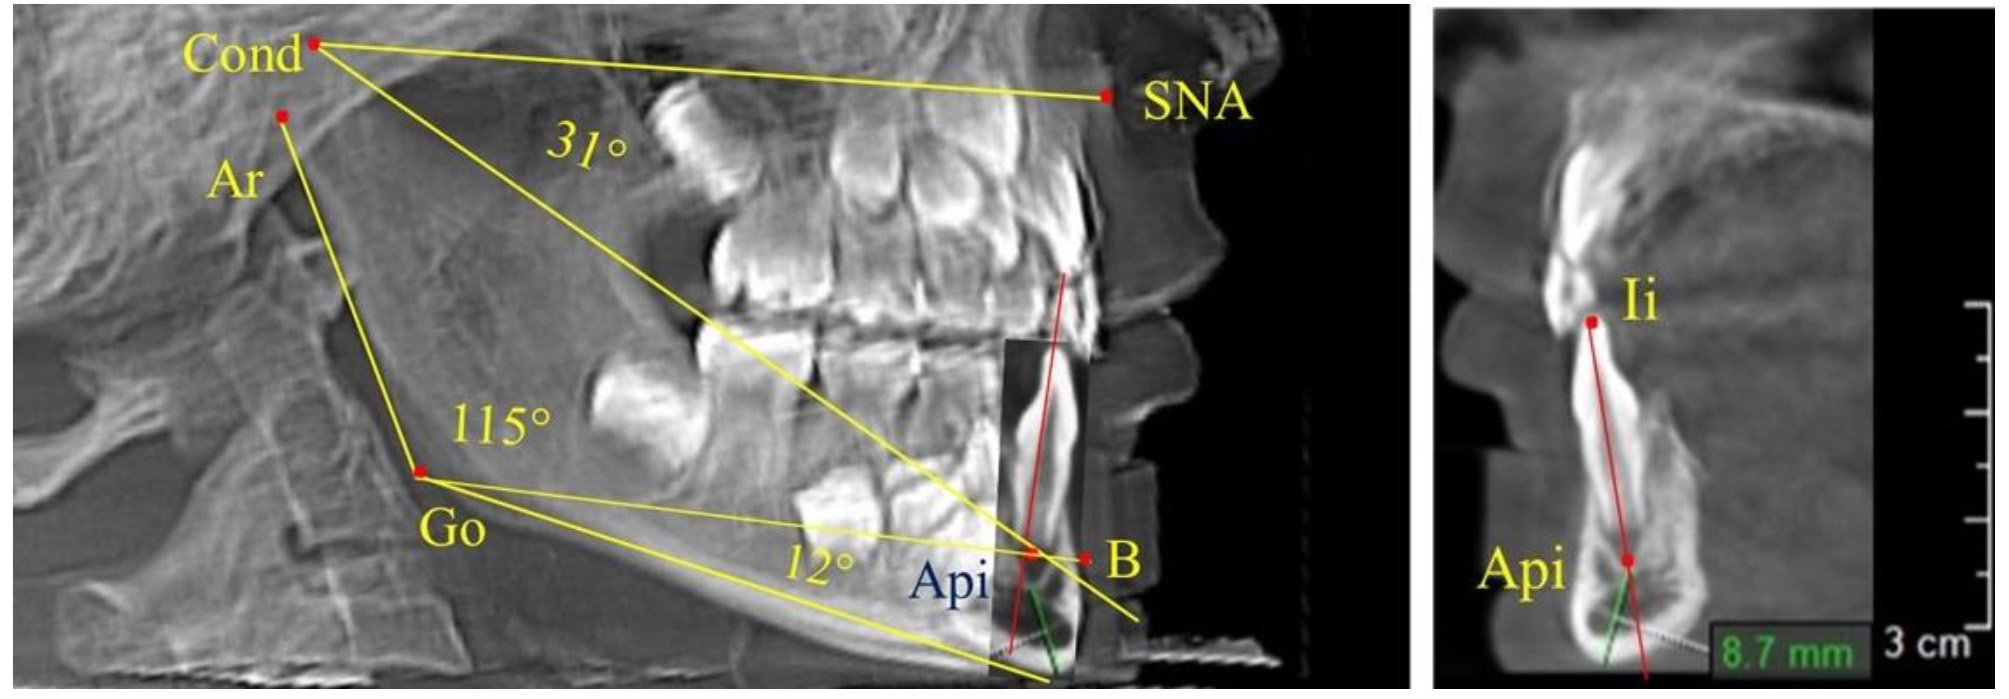

Особенность анализа телерентгенограммы в периоде сменного прикуса заключалась в том, что наслоение зачатков постоянных зубов затрудняло определение апикальной точки нижнего резца. В подобных случаях использовали метод совмещенного анализа телерентгенограммы с фрагментом томограммы, на котором, также как и на телерентгенограмме, определяли положение резцовой и апикальной точек с построением условной вертикали, которая служила ориентиром для совмещения фрагментов (рис. 2).

Рис. 2. Особенности совмещения телерентгенограммы с фрагментом томограммы в сменном прикусе

Таким образом, в периоде молочного прикуса с оптимальными окклюзионными соотношениями, несмотря на линейные размеры в вертикальном и сагиттальном направлении, которые, безусловно, меньше параметров взрослых людей, величина основного угла гнатической части лица SNA-Cond-Api соответствовала параметрам людей с полностью сформированным физиологическим прикусом постоянных зубов. Анализируя данные рентгенограмм детей в периоде сменного прикуса, отмечено, что величина основного угла гнатической части лица SNA-Cond-Api, так же как в молочном и постоянном прикусе, в норме составляла от 28 до 32°. В то же время угол нижней челюсти и его составляющие отличались вариабельностью параметров при различных показателях нижнечелюстного угла. Достоверных различий угла гнатической части после смены нижних медиальных резцов и прорезывания первых постоянных моляров (4 ребенка) не было; происходил очередной этап подъема высоты прикуса и увеличение линейных размеров костей гнатической части, однако угловые параметры были относительно стабильны. После смены всех резцов и замены первых молочных моляров первыми премолярами (6 человек) увеличивались линейные размеры при сохранившихся угловых показателях гнатической части лица (рис. 5).